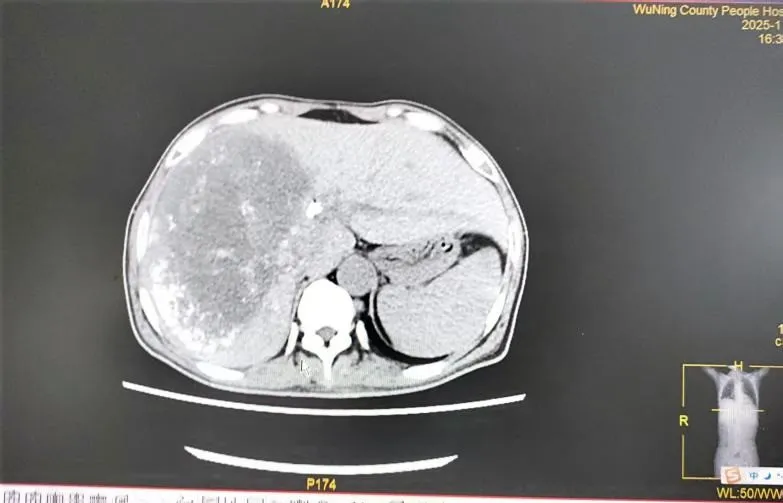

对于已失去手术机会的晚期肝癌伴梗阻性黄疸患者,肿瘤科介入团队发挥了关键作用。一例直肠癌肝、肾上腺多发转移导致严重黄疸、肝功能受损的患者,情况危急。团队首先行“经皮胆管支架植入+引流术”,快速解除胆道梗阻,改善肝功能。待患者状况稳定后,又为其制定了序贯的“肝动脉灌注化疗联合栓塞术(HAIC+TACE)”方案。经过数次介入治疗,患者肝内转移灶明显缩小,黄疸完全消退,肿瘤标志物显著下降,生活质量得到极大改善。这凸显了我院在晚期肿瘤并发症处理及局部介入综合治疗方面的强大技术支撑。

2025年11月20日CT示: